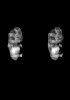

Carnegie Stage 20 (50 post-ovulatory days)

Most embryos at stage 20 are approximately 50-51 postovulatory days old and measure 21-23 mm in length. Distinguishing criteria for this stage include upper limbs slightly bent at the elbows, short stubby fingers, hands curving over the cardiac region but still far apart from each other, and a fringe-like vascular plexus that marks growth centers laterally in the superficial tissues of the head.

MRI Slice Selector

Mouse: click on a line below to select a view

Finger: tap a line below with a very light touch